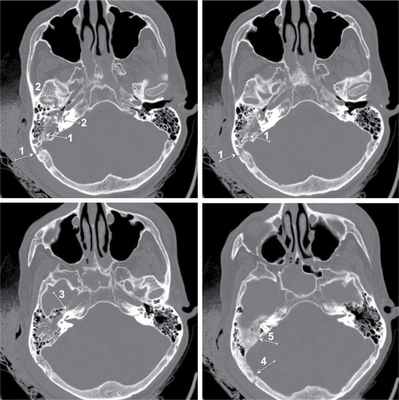

а - Переломы височной кости: 1 - продольные переломы; 2 - поперечный перелом.

Объективное состояние больного при поступлении — кома III, шкала комы Глазго — 3 балла, пульс на сонных артериях — 40—50 уд/мин, слабого наполнения, аритмичный, АД — 80/40 мм рт.ст., мидриаз D=S, атония, арефлексия, цианоз кожи и слизистых оболочек. Доставлен в экстренную операционную, где продолжена интенсивная терапия. Проведено комплексное обследование, консультирован ЛОР-врачом, челюстно-лицевым хирургом. Выполнена фибробронхоскопия, первичная хирургическая обработка ран левого века и слизистой оболочки верхней губы. Отмечалась отогемоликворея справа, симптом «пятна» положителен. Гемодинамика на фоне вазопрессорной поддержки адреналина: пульс 90 уд/мин на сонных артериях, слабого наполнения, АД — 90/60 мм рт.ст., при увеличении показателей гемодинамики отмечалось обильное кровотечение из наружного слухового прохода, наложена асептическая повязка. Выполнена компьютерная томография головного мозга: линейный перелом каменистой части височной кости, проходящий через сигмовидный синус, канал внутренней сонной артерии, стенки наружного слухового прохода; объемного воздействия на головной мозг не выявлено, базальные цистерны не деформированы (см. рисунок). Компьютерная томограмма пирамидок височных костей больного Е. (аксиальная проекция, режим «костного окна»). Стрелками указана линия перелома, проходящая через борозду сигмовидного синуса (1), стенки наружного слухового прохода (2), канал внутренней сонной артерии (3), затылочную кость (4), верхнюю грань пирамидки височной кости (5).